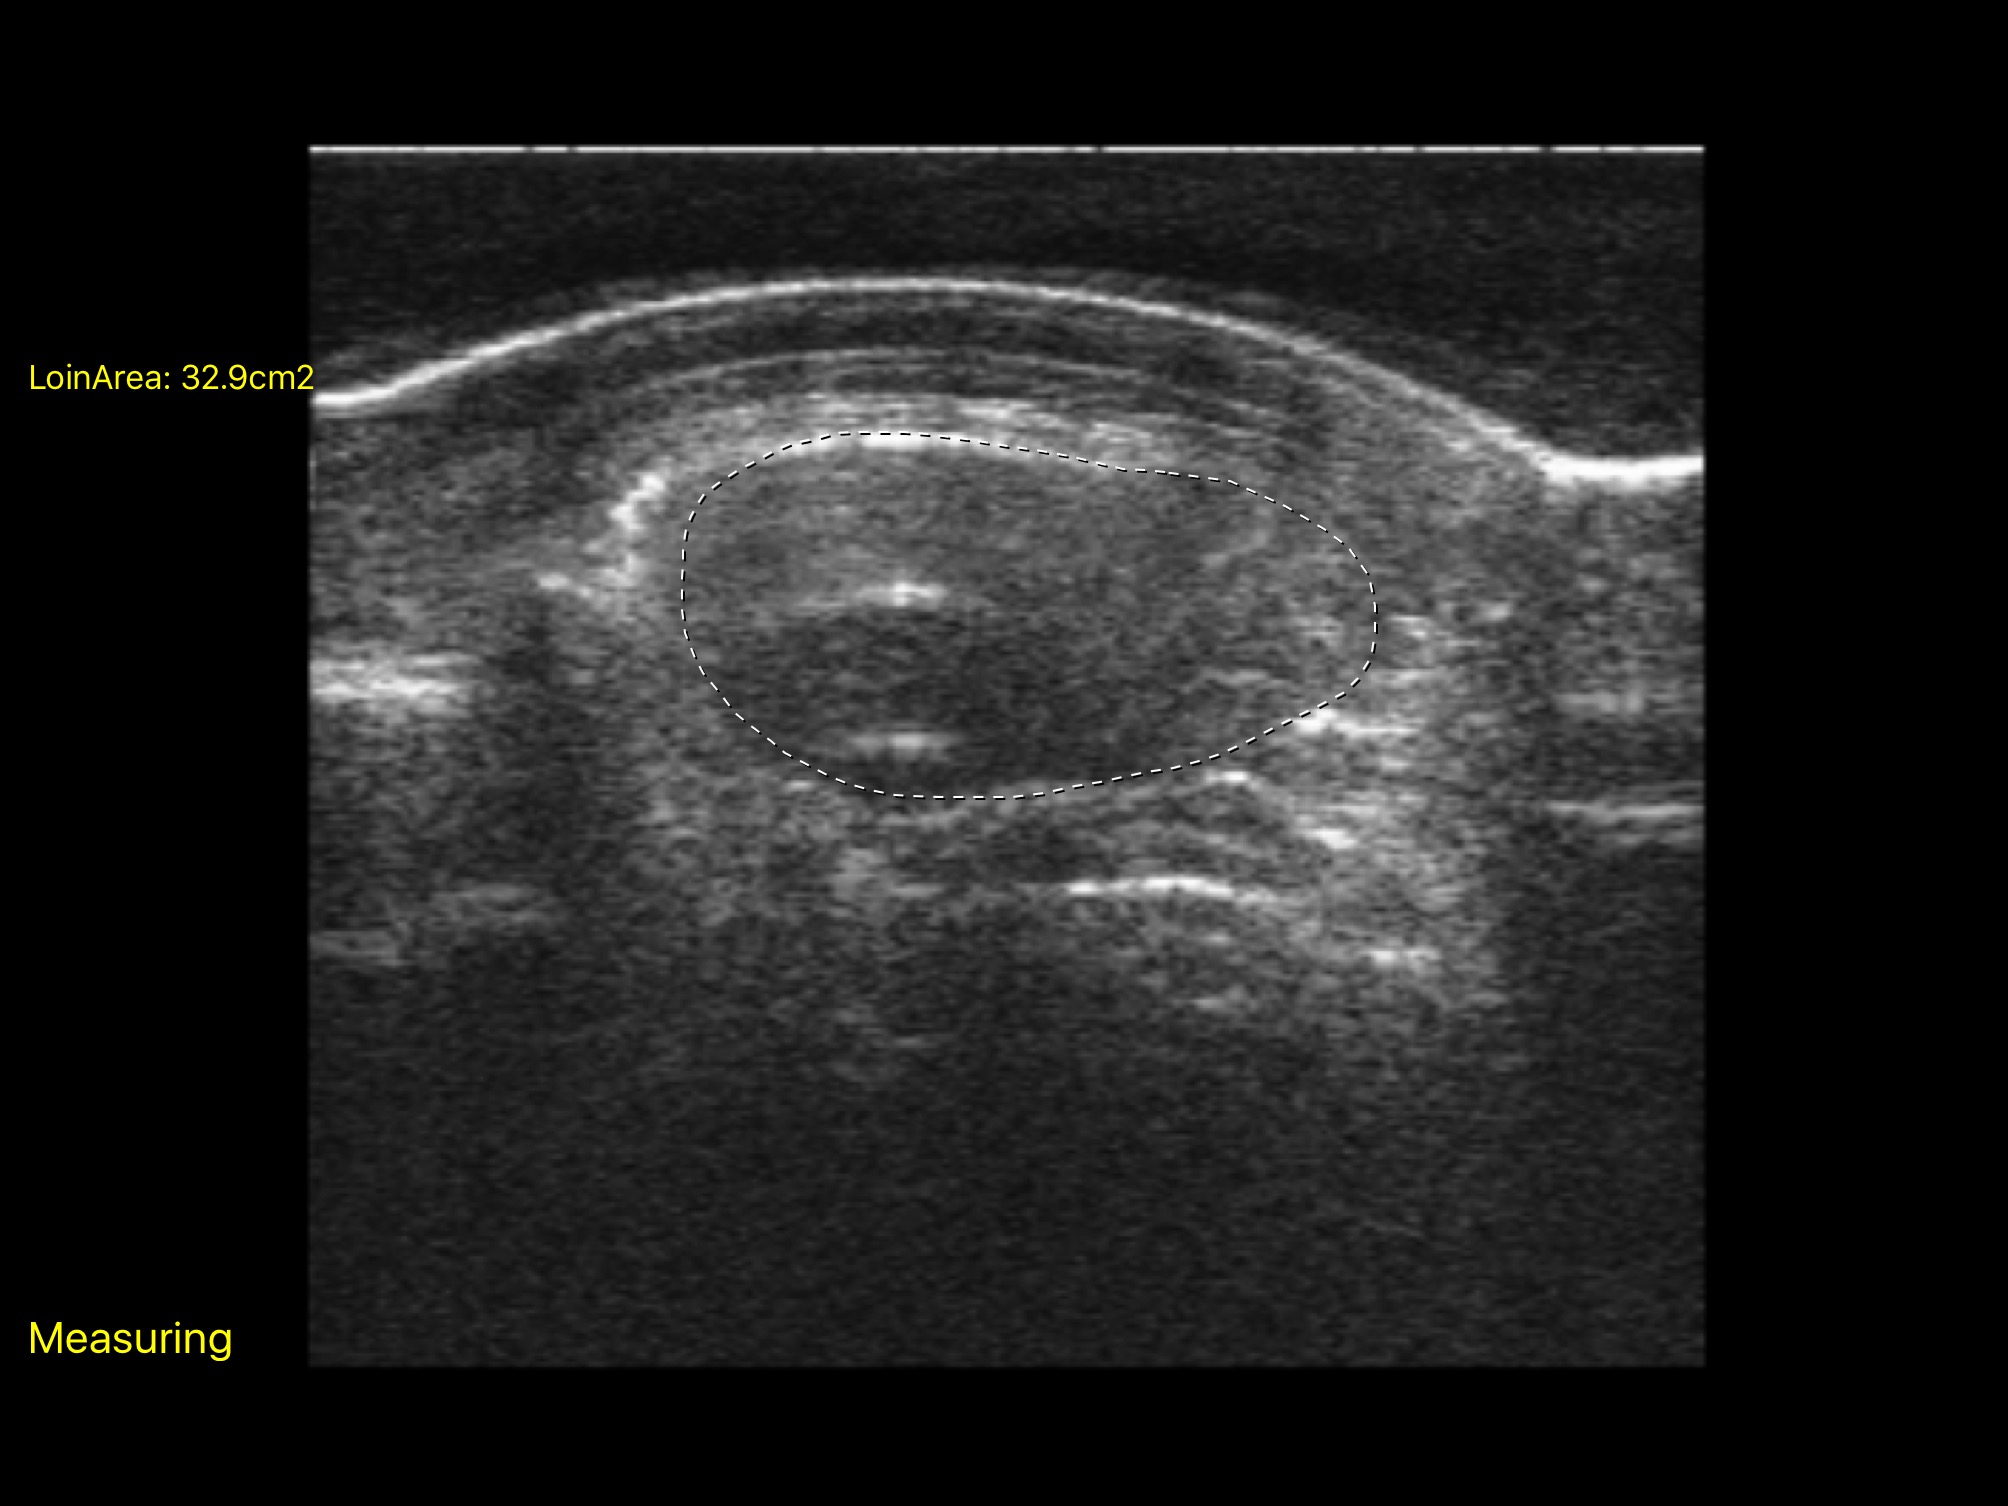

測量腰眼面積 超簡單!! 由iPad手繪腰眼輪廓邊緣,立即計算數值

‧ 三款測量 - 一. 背脂 、二. 腰眼深度/背脂厚度 、三. 腰眼面積計算。